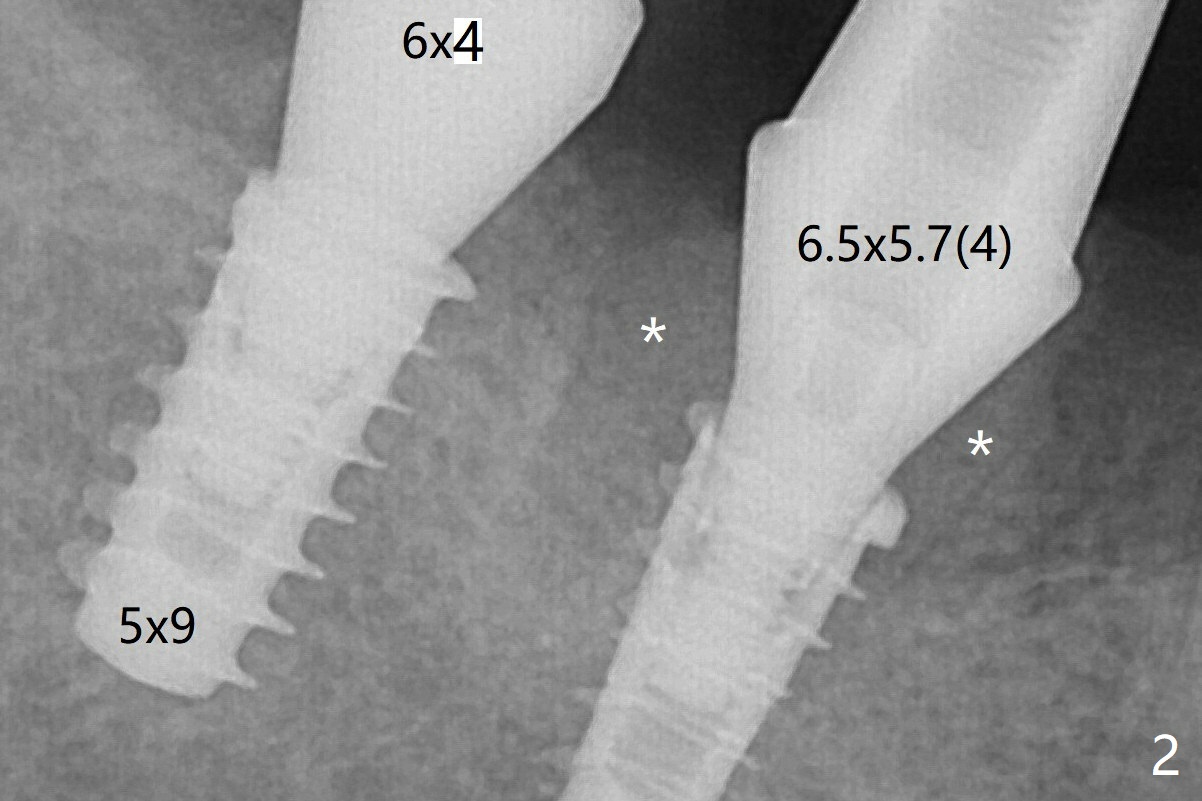

Note bone growth, especially at #30, 2.5 and 4 months postop (Fig.3,4). In fact the abutments are incompletely seated. The crown of #30 is loose with foul smell 2 years 8 months post cementation. It is painful to reinsert the crown/abutment after proximal reduction. A healing abutment is placed (Fig.5). When the incompletely seated abutment at #31 is removed, there is also smell. After separation from the crown, the abutment of #31 returns to the site with change in insertion position, while a smaller abutment has to be used at #30 (Fig.6) due to use of the small healing abutment earlier (Fig.5). A good piece of news is the presence of the bone between the implants (Fig.5,6 *), which contributes to interimplant papilla.